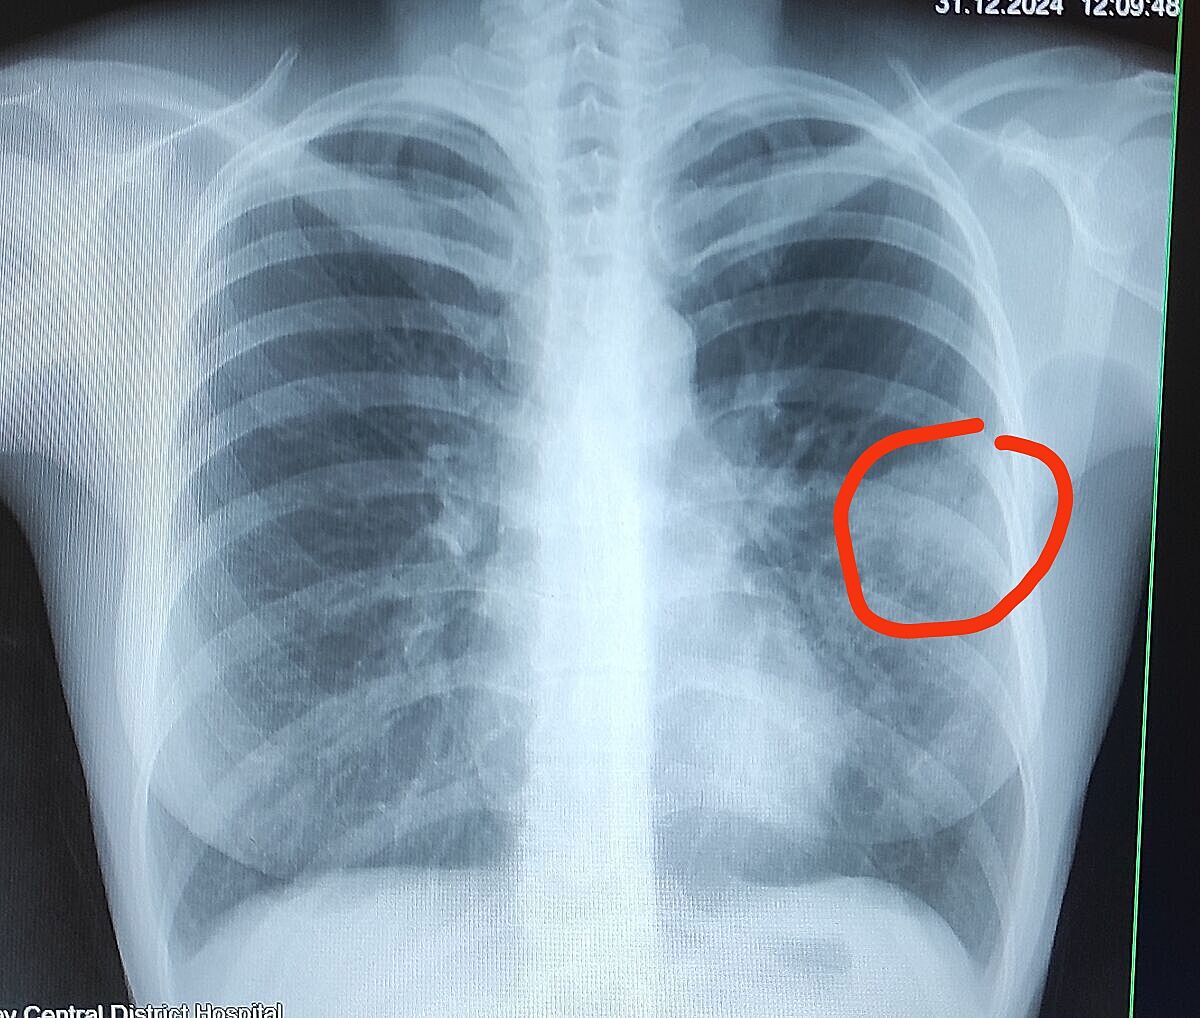

Это описание рентгена лёгких, последние слово пневмония, это всё что я там поняла. Кто разбирается, что там написано?

Серце норма.В середньому легеневому полі лівої легені спостерігається інфільтративна тінь без чітких контурів.

Ds:лівостороння пневмонія